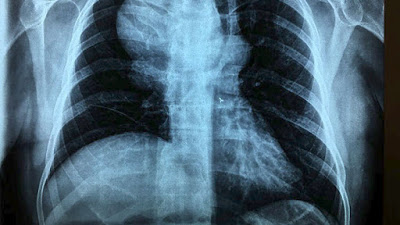

«Σύμφωνα με τη διεθνή βιβλιογραφία, έχουν δημοσιευθεί συνολικά 50-60 μεγάλα ανευρύσματα, εκ των οποίων αυτό που αντιμετωπίσαμε είναι το μεγαλύτερο παγκοσμίως. Τα μετατραυματικά ανευρύσματα είναι εξαιρετικά σπάνια και γι΄ αυτό πολλές φορές υπάρχει αδυναμία διάγνωσης. Το συγκεκριμένο προκλήθηκε από τραύμα το 2001 και μεγάλωνε συνεχώς και ενώ ο ασθενής είχε τη συμπτωματολογία, αλλά και ευρήματα στην ακτινογραφία, δεν οδήγησαν στη διάγνωση του ανευρύσματος» αναφέρει ο αγγειοχειρουργός Νικόλαος Σαρατζής.